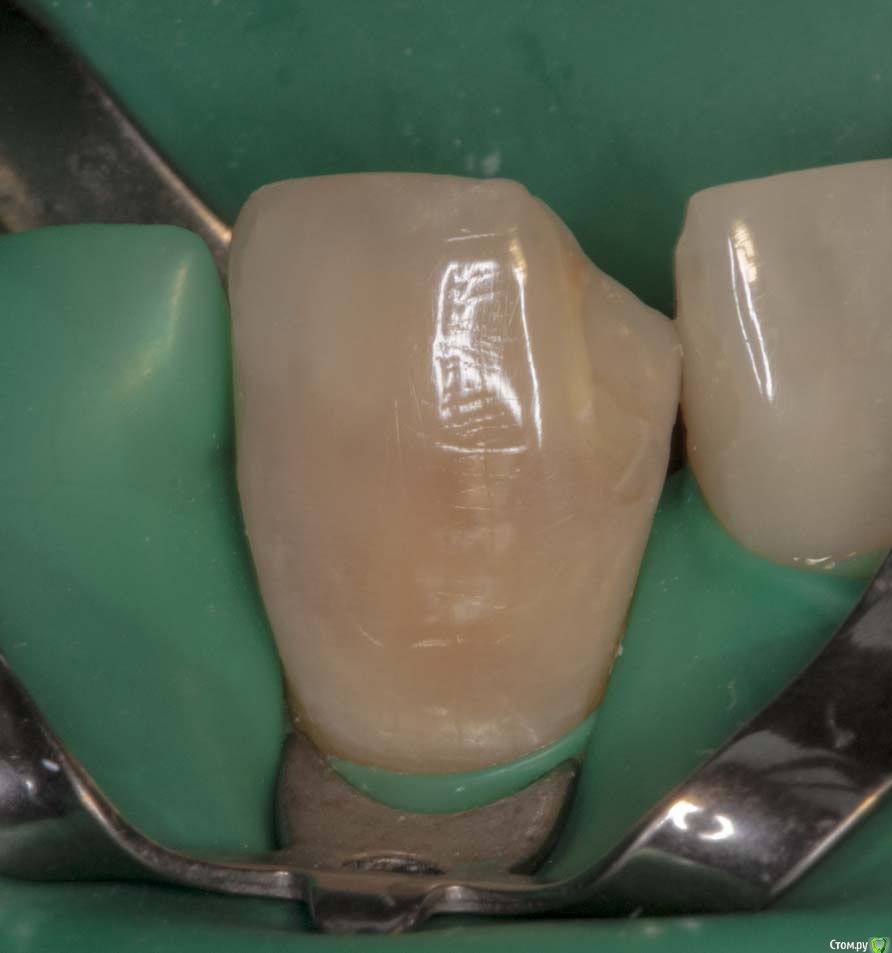

M@estro Опубликовано 19 марта, 2015 Автор Поделиться Опубликовано 19 марта, 2015 (изменено) Ну вот как - то так. Жалобы на эстетику. Зуб асимптоматичен, но я перебрал, уж сильно неплотно там было. В анамнезе резекция верхушки корня лет 7 назад. http://s016.radikal.ru/i334/1503/78/5a6341839e0c.jpg http://s013.radikal.ru/i323/1503/04/31d3729756de.jpg http://s018.radikal.ru/i524/1503/a9/79248c45e74b.jpg Изменено 19 марта, 2015 пользователем M@estro 13 Ссылка на комментарий